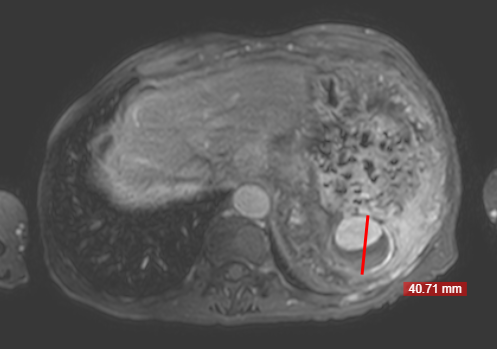

Nome do procedimento: EMBOLIZAÇÃO DE ARTÉRIA ESPLÊNICA

-COMORBIDADES: HAS; DISTÚRBIO VENTILATÓRIO OBSTRUTIVO LEVE COM CAPACIDADE VITAL REDUZIDA; CÂNCER DE PELE; HÉRNIA INGUINAL À ESQUERDA; HIPERTENSÃO PORTAL E VARIZES ESOFÁGICAS ASSOCIADA A ESQUISTOSSOMOSE HEPATOESPLÊNICA; CATARATA

Exames séricos e de imagem:

HEMOGRAMA: Eritrocitos 3,49 Milhoes/mm³, Hemoglobina 12,6 g/dL, Hematocrito 38,3%, VCM 109,7 fL, Plaquetas 43000 /mm³ (Diminuidas em lamina)

Galeria de imagens: 4421,4422